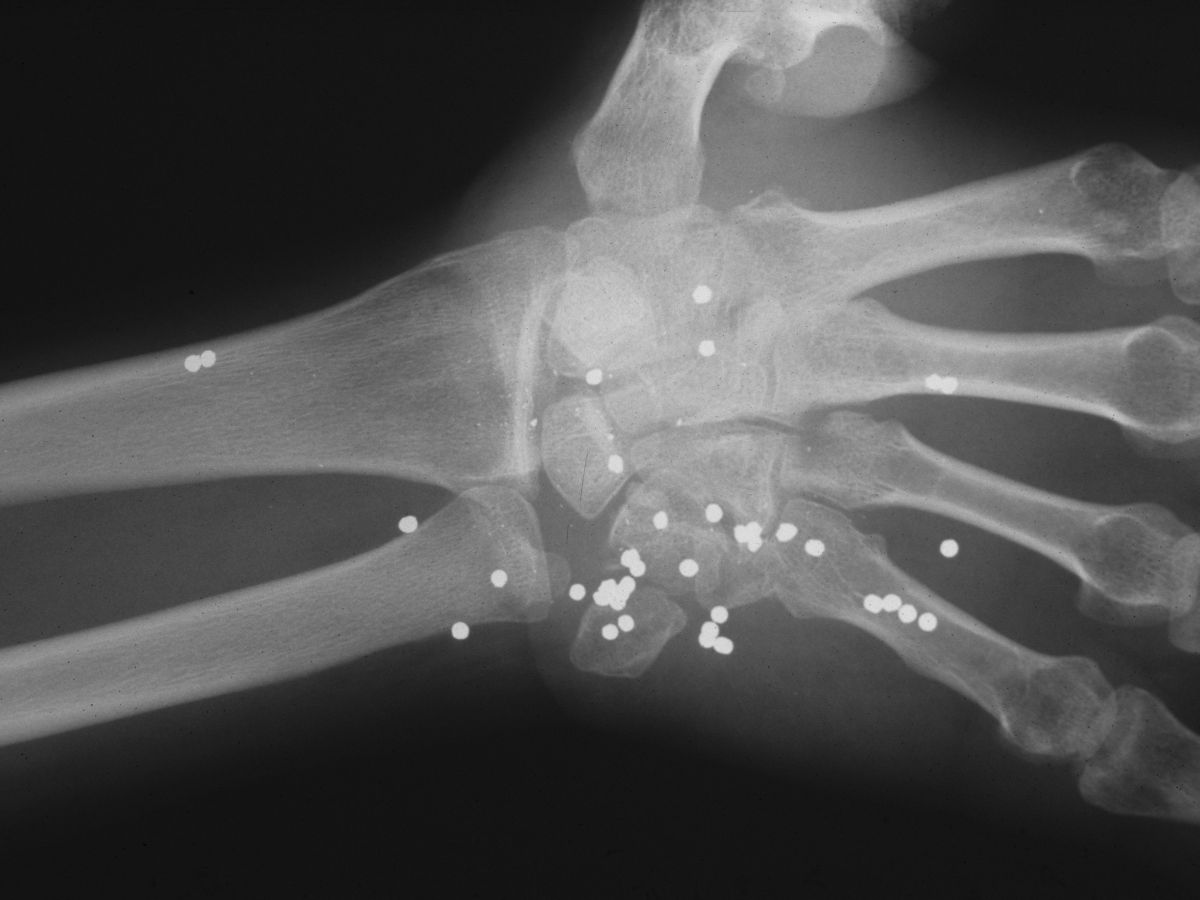

This young adult presented one year after sustaining a close range gun shot injury of his left palm, which had been treated with local wound care. No records were available, and he was vague about the details of the injury. He had complete median nerve loss, a stiff hand and a healed wound in the central proximal palm. Xrays were consistent with retained shotgun pellets, most likely turkey shot (#4 shot, 135 pellets per cartridge).

Postop xrays showing lead debulking.